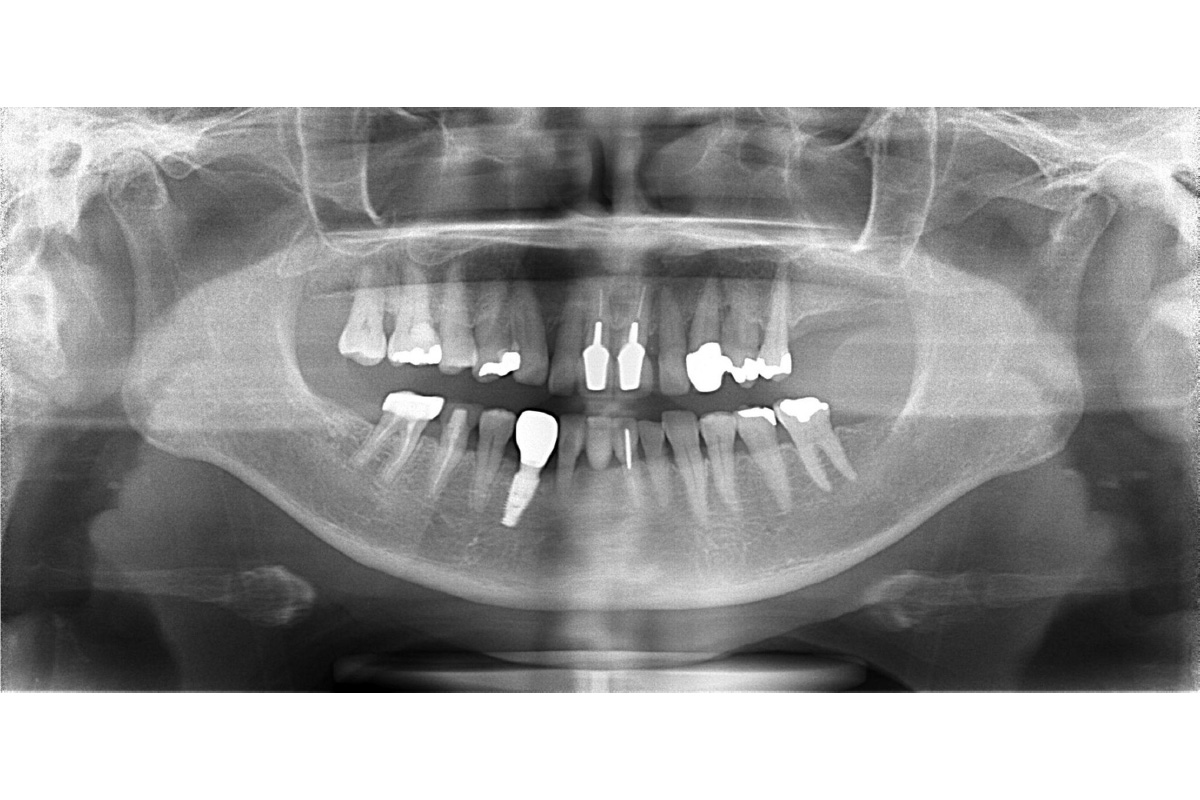

治療前

| 主訴 | 左下の歯を入れ歯以外で治したい。前歯のブリッジはそのままで治したい。 |

| 期間 | 5ヵ月 |

| 費用 | 566,500円(治療時) |

| 治療内容 | 骨造成 結合組織移植術 インプラント治療 |